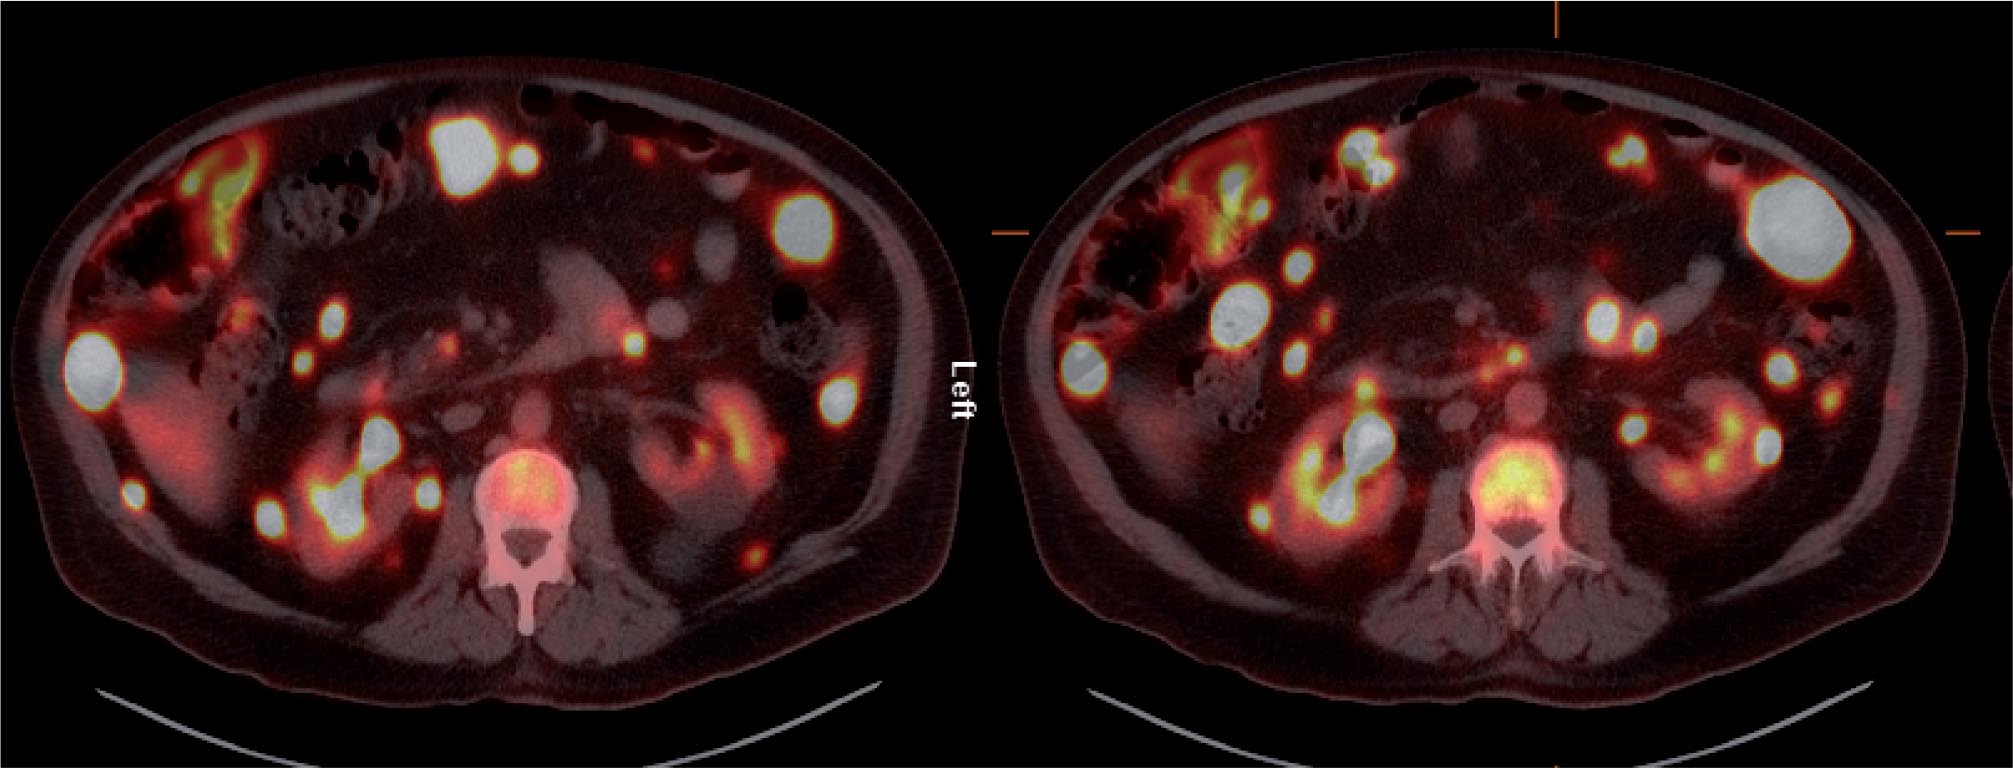

The patient was referred for 18F-FDG-PET/CT the next day to further evaluate the disease extent. A whole-body PET/CT was performed 60 min after the intravenous injection of 629 MBq (17 mCi) 18F-FDG. The study showed multiple hypermetabolic foci throughout the body (Figure 1). There was a large soft tissue mass in the right lower lobe with increased 18F-FDG uptake; the maximum standardized uptake value (SUVmax) of this lesion was 38.0. Also, there were multiple hypermetabolic nodules in the thyroid, gastric mucosa, pancreas, and both the adrenals. Both kidneys contained exophytic lesions with increased 18F-FDG uptake (Figure 2). A circumferential soft tissue mass in the esophagus was hypermetabolic as well. Additional FDG-avid nodules and masses were also found in the peritoneum and omentum; the largest of these had a SUVmax of 68.0. Intense FDG uptake was observed in multiple subcutaneous and intramuscular nodules throughout the body, some of which were thought to represent lymph nodes. Brain magnetic resonance imaging was performed on the same day, which revealed five metastatic lesions measuring up to 1.5 cm in the left frontal lobe, anterior right parietal lobe, and right temporal lobe. At this point, there were multiple candidate lesions for the primary malignancy, such as lung, esophagus, melanoma, or an aggressive lymphoma.

Figure 1. Maximum intensity projection (MIP) images in anterior and posterior views of the 18F-FDG PET/CT images showing multiple hypermetabolic foci of increased FDG uptake throughout the body, most likely representing widespread metastatic disease.